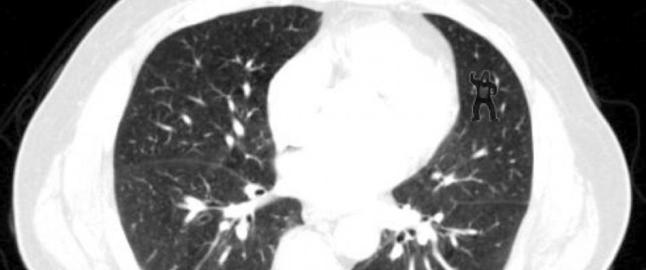

Kan du finne gorillaen som danser i disse lungene?

I så fall er du skarpere enn hele 83 prosent av radiologene som gransket CT-bildet. Les mer